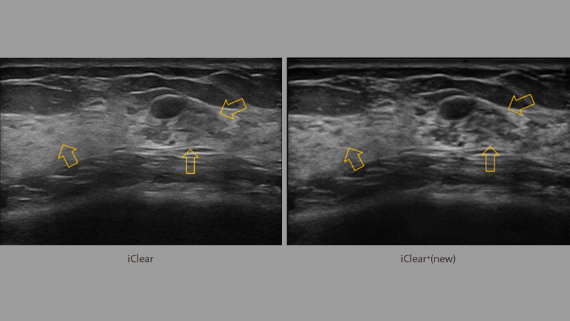

Immagini cliniche